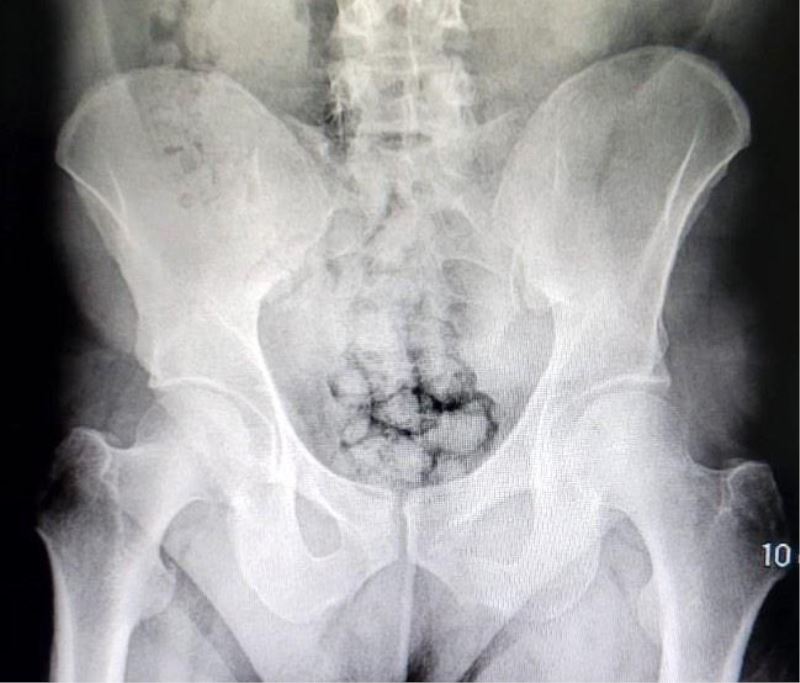

Kayseri İl Emniyet Müdürlüğü Narkotik Suçlarla Mücadele Şube Müdürlüğü ekipleri uyuşturucu madde ticareti yapan iki yabancı uyruklu şahsı takibe aldı. Ekipler, hareketlerinden ve mide bulantılarından şüphelendiği şahısları hastaneye götürdü. Burada röntgen çekinen şahısların midesinde farklı maddeler tespit edildi. Yapılan tıbbi müdahalede şahısların metamfetamin kapsüllerini yutarak midelerinde saklandığı belirlendi. Kayseri Valisi Gökmen Çiçek, operasyonla ilgili olarak, "Ne yaparlarsa yapsınlar Kayseri Emniyetinden kaçamayacaklar. İlimize uyuşturucu sokmak için denedikleri her yol emniyetimizin dikkati sayesinde başarısızlığa uğratılıyor. Bu sefer metamfetamin kapsüllerini midelerinde saklayarak ilimize sokmaya çalıştılar. Emniyetimizin dikkati sayesinde kıskıvrak yakalandılar. Gençlerimizi zehirlemelerine izin vermeyeceğiz. Tebrikler Kayseri Emniyet" ifadelerini kullandı.